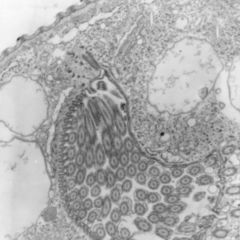

Als Intrazellularraum (IZR) wird in der Pharmakologie der Verteilungsraum innerhalb des menschlichen Organismus bezeichnet, der aus der Gesamtheit aller von Zellmembranen umschlossenen Zellbestandteile gebildet wird und daher also vor allem aus den Zellorganellen, der Zellflüssigkeit und unterschiedlichen Einschlüssen besteht. Es handelt sich beim IZR weder um einen zusammenhängenden, noch – wegen ständiger Austausch- und Umbauprozesse – um einen eindeutig abgegrenzten Raum, sondern um eine modellhafte Auffassung, die in der Pharmakokinetik praktische Bedeutung hat.